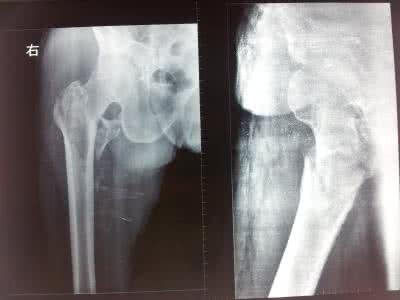

股骨粗隆间骨折

股骨粗隆间骨折是骨科中比较常见的一种疾病,随着我国老龄化的到来,为使老年朋友对高龄股骨粗隆间骨折的相关知识及防治策略有所了解,这里从六个方面介绍高龄股骨粗隆间骨折的相关知识,希望老年朋友能从中受益。

由于粗隆间局部以松质骨为主,高龄老人均有明显的骨质疏松,伤后容易发生不稳定的粉碎性骨折。同时,高龄老年患者,伤前常伴有各种内科疾病,无论采取何种治疗方式,对老年患者都具有风险。